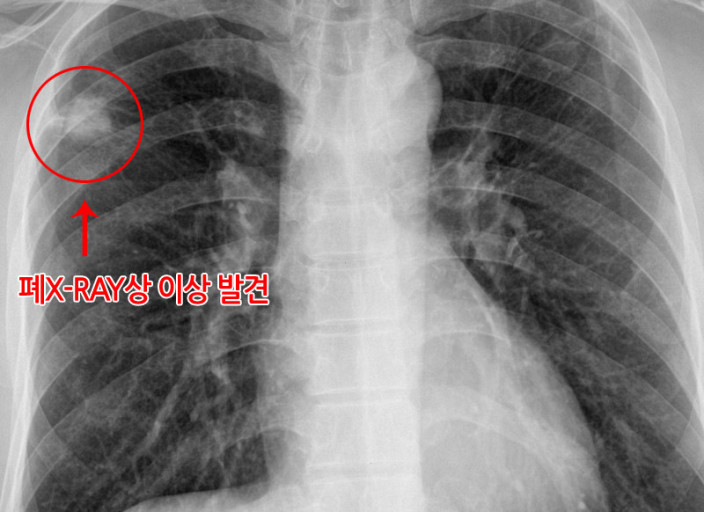

폐암 증상에는 기침, 체중 감소 흉통, 혈담 즉 피가 섞인 가래, 호흡곤란 등이 있지만, 위 증상은 다른 폐 질환에서도 나타날 수 있는 증상으로 구분하기가 어렵다. 그리고 폐암 초기에는 특별한 증상이 없는 경우가 대부분이라서 최근 흡연뿐 아니라 미세먼지 등 여러가지 요인으로 폐암이 발생하는 경우가 많아 정기검진으로 조기에 발견하는 것이 중요며 폐암 검진을 위해서는 특히나 저선량 흉부 CT를 촬영하는 것이 좋다라고 전문가들은 말하고 있습니다..

보통 숨소리는 크게 들리지 않지만, 목이나 폐 부분에 뭐가 걸린 느낌이 나듯이 숨소리가 거칠어지는 걸 느낍니다.면 폐에 문제가 생겼을 확률이 높다. 꼭 내원해 엑스레이를 촬영해 보는 게 바람직합니다..